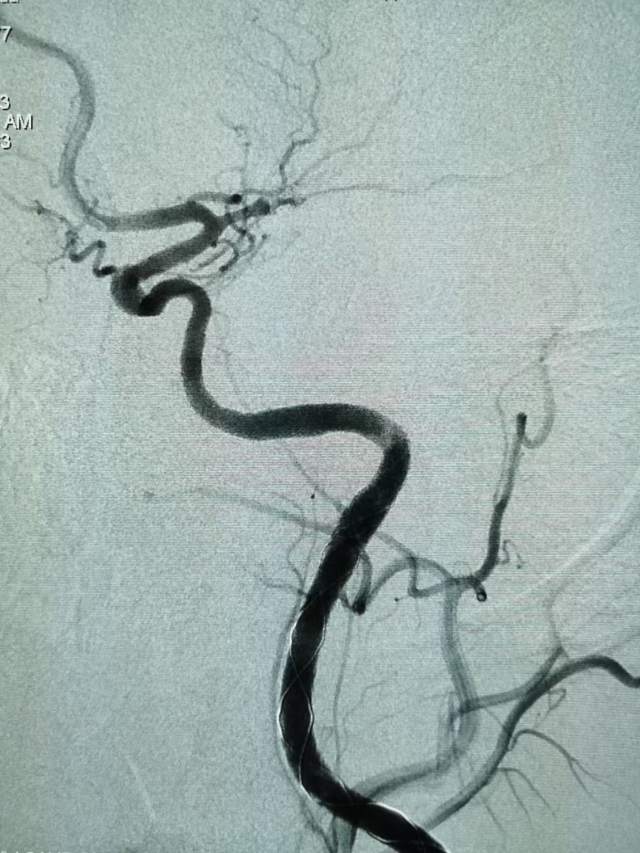

遗留右侧肢体残疾,尽管卧床康复3个月,肢体也只能在床上平移,无法抬离床面,完全性失语,不能说话。家属老爸经人介绍辗转收入我科,看看能否得到进一步的改善。第一次晨间病房查房,看到纯朴、善良、苍老的老爸站在床边,向我们不紧不慢的诉说着女儿的病情,年轻秀丽的女儿静静躺在床上,一言不发(完全性失语),想到独生子女家庭在老年突然遭遇失独、残疾等意外后,本是年轻人照顾老年人的季节,现如今却成了白发人弓着背照顾残疾的黑发人,让人心中一阵苍凉和心酸。患者左侧大面积脑梗塞三个月,右侧肢体肌力只有2级,完全性失语;左侧大脑前动脉向左侧大脑中动脉代偿供血,基于上述情况,可能能够做的外科工作并不多,进一步康复的希望也不大。尽管如此,我们还是认真的对患者进行了详尽细致的评估,看看能否找到突破点。造影发现患者颈内动脉起始部存在颈动脉蹼(可能是三个月前引起梗塞的原因,图3)

还有两处隐约可见的颈动脉夹层,造影期间血管局部构型短时间内出现改变,提示夹层影响远端血流,修复夹层对患者至关重要

于是一个支架重建两处夹层和颈动脉蹼(花钱少,一个支架解决3个病变),手术顺利。